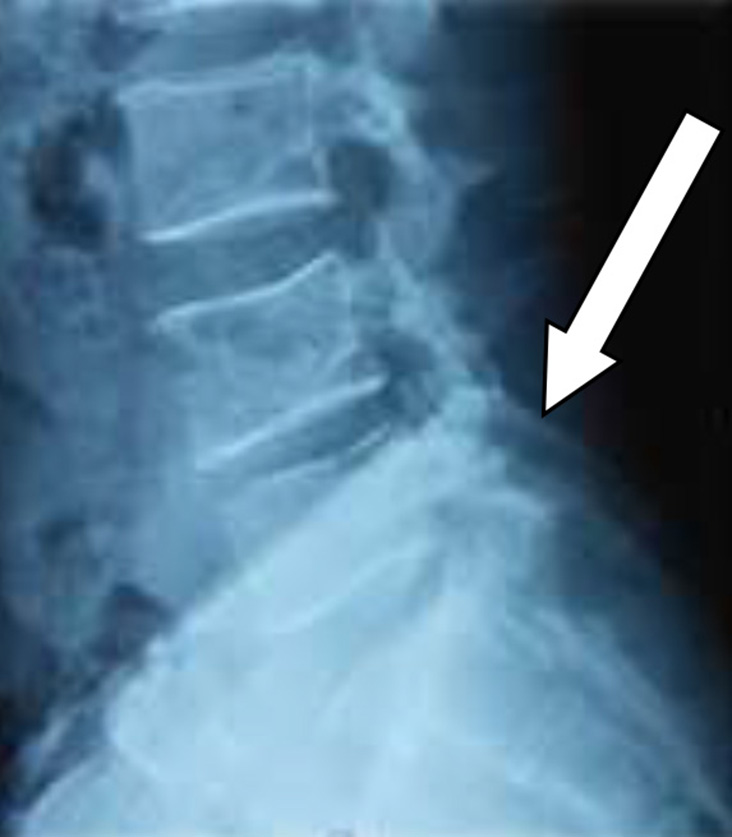

Following spinal anesthesia, patients were positioned prone. A midline incision was made one level above and below the involved segment. C-arm intensifier was utilized, especially when sacralization or lumbarization was identified in preoperative imaging. The spine and laminae were exposed, centering on the affected disc space. Portions of the spinous process and interspinous ligament were excised. The lower halves of both laminae were removed until the epidural fat became visible through the ligamentum flavum in the midline. (Fig. 1). The ligamentum flavum was excised bilaterally, and in certain cases, the overhanging portions of the hypertrophied medial facets were removed using a Kerrison punch. A standard technique was employed for discectomy, ensuring the complete removal of all visible disc material. Both nerve roots were examined for any additional compressive elements before they entered their respective foramina. For L5-S1 disc prolapse, only ligamentum flavectomy was performed with limited laminectomy (even less than the lower half) to facilitate adequate discectomy. The wounds were closed in layers after achieving proper hemostasis. For illustration images from a case of L5-S1 disc prolapsed are presented(pre-operative MRI and post operative X-ray) (Fig. 2-4).

Fig. 4. X-ray of the LS spine (anteroposterior (A) and lateral (B) views) done postoperatively demonstrating the post laminectomy defects(indicated by arrows)